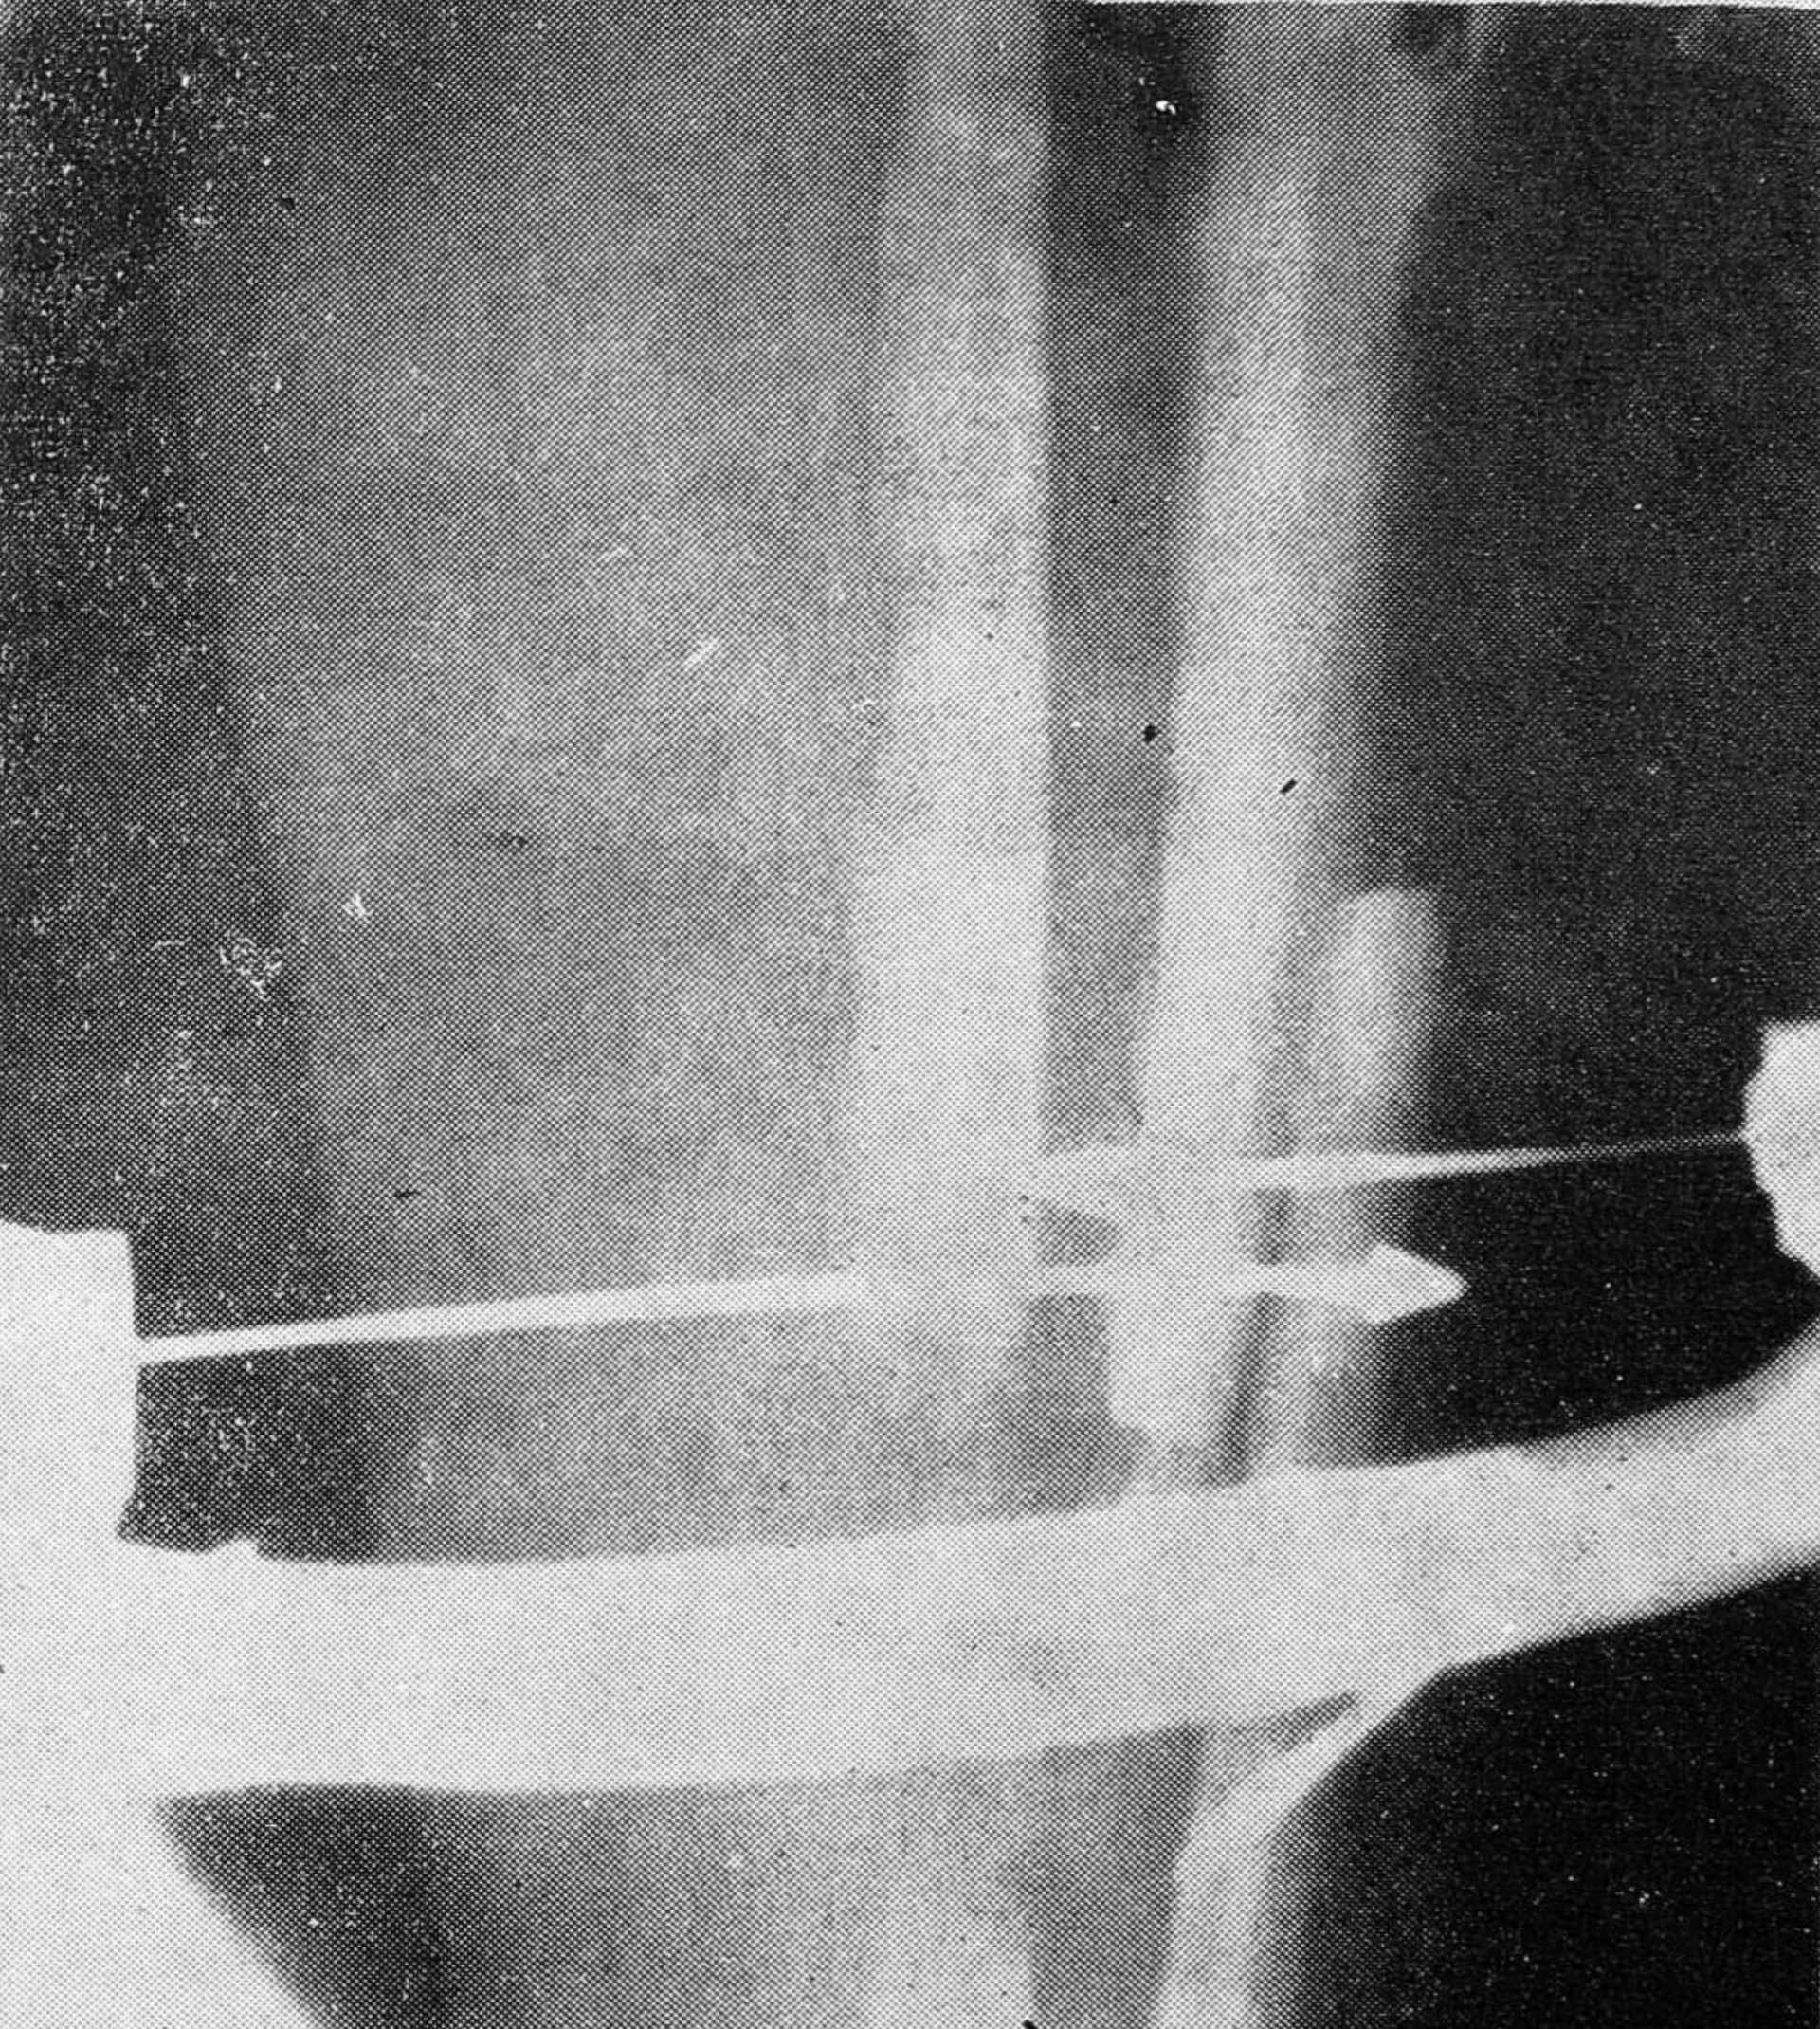

С целью наименьшего нарушения питания фрагментов удлиняемой кости мы резко сузили показания к типичной Z-образной остеотомии (особенно на голени), требующей широкого выделения отломков. В настоящее время мы предпочитаем оперативный доступ, позволяющий производить косую остеотомию большеберцовой кости во фронтальной плоскости на уровне верхнего метадиафиза при минимальном отделении окружающих тканей с обнажением лишь наружной поверхности кости (в то время как защитник подводится поднадкостнично с противоположной, внутренней стороны ее через небольшой дополнительный разрез по передне-внутренней поверхности верхней трети голени, рис. 1). Характерно, что во всех случаях выполнения остеотомии по вышеуказанной методике (5 больных) удлинение протекало без сколько-нибудь значительных осложнений.

Рис. 1. Доступ при косой остеотомии большеберцовой кости с целью ее удлинения.